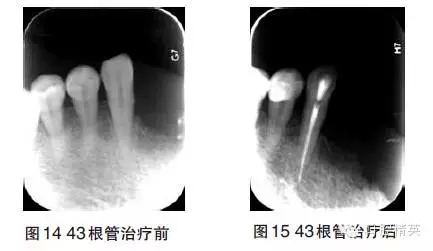

9、治療階段――根管治療

11、12、14、21、22、25、26、27、28、31、32、35、41、42、47、48缺失,剩余牙槽嵴較豐滿。13、15、16、17、18、23、24、33、34、36、37松動(dòng)Ⅰ~Ⅲ°。PD 5~9mm。38、46松動(dòng)Ⅰ°,PD3~6mm,根分叉病變Ⅰ~Ⅱ°。43松動(dòng)Ⅰ°,PD2~4mm,過(guò)長(zhǎng)。44、45頰面楔狀缺損,無(wú)松動(dòng),PD2~3mm。